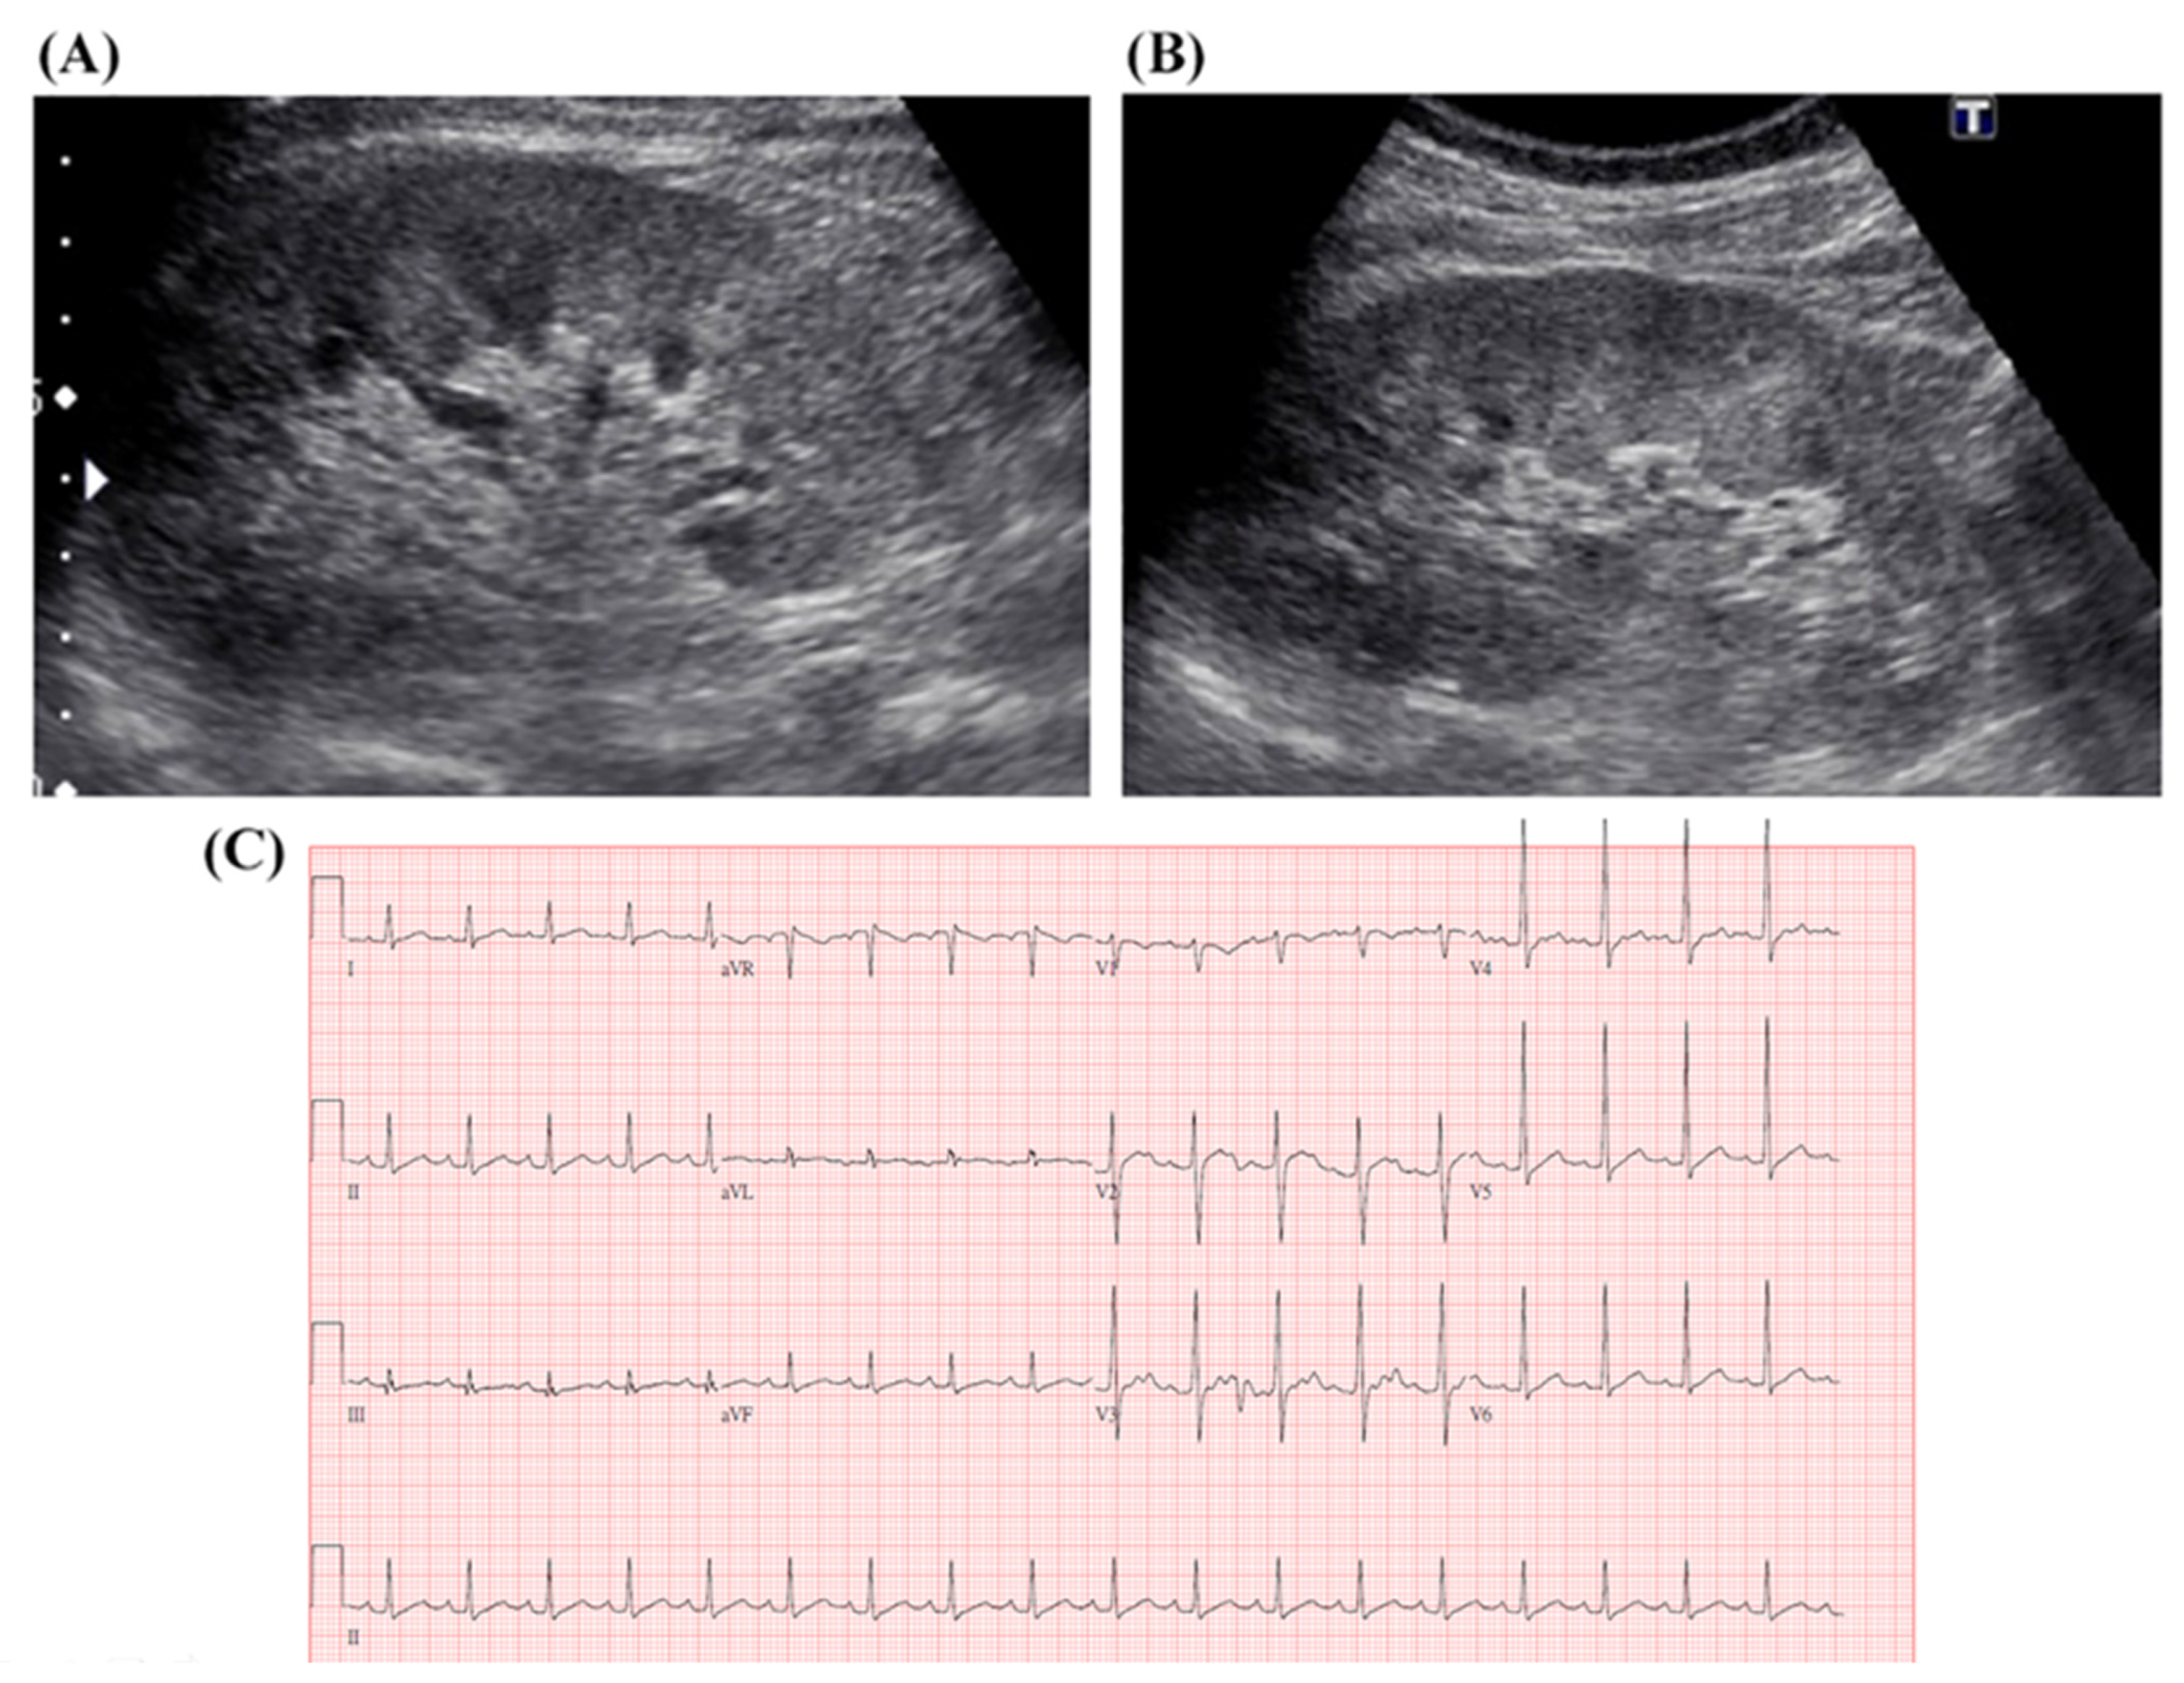

3.1. Clinical Presentation and Initial Treatment Response of Leptospirosis

3.2. Intensive Care Unit Admission and Evolving Treatment Strategies of Leptospirosis